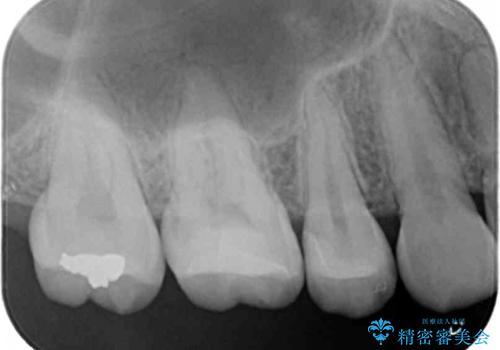

- 奥歯の銀の詰め物を白くしたいとのことで来院されました。

- 右上7 セラミックインレー 77,000円費用は治療当時の料金となります

今回は大きな虫歯もなかったため、1回当たり30分程度の治療時間で計2回の来院回数で治療を終えることができました。